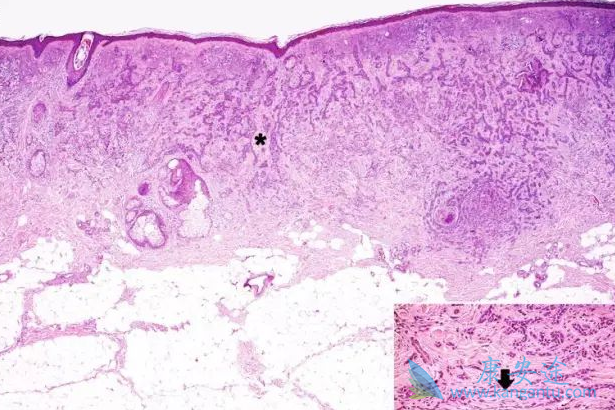

基底细胞癌是头颈面部较常见的恶性肿瘤,跟日照有很大关系。主要表现为褐色结节,可以表现为中央破溃,经久不愈。一般较少发生淋巴结转移。可以有局部较深的破坏。美国国家癌症研究所的数据显示,美国每年约有百万人接受基底细胞癌治疗。基底细胞癌治疗主要采取手术切除,术中行快速冰冻检查,确认周围及基地切缘阴性没有肿瘤细胞残留,根据缺损选择修复方式。